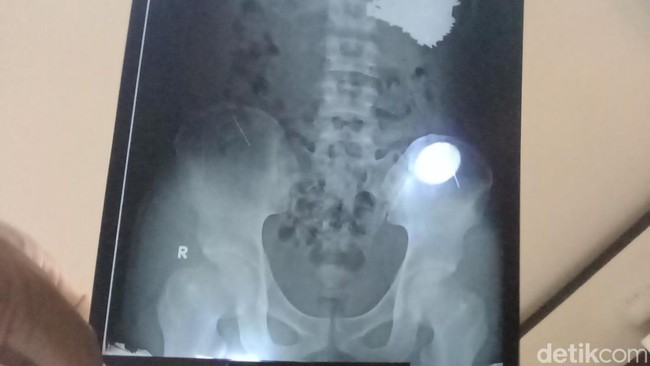

Indramayu - Seorang pemuda dengan gangguan jiwa menelan puluhan paku dengan sengaja di Kabupaten Indramayu, Jawa Barat. Dokter pun berhasil mengeluarkan 70 paku yang bersarang di tubuh pemuda tersebut.